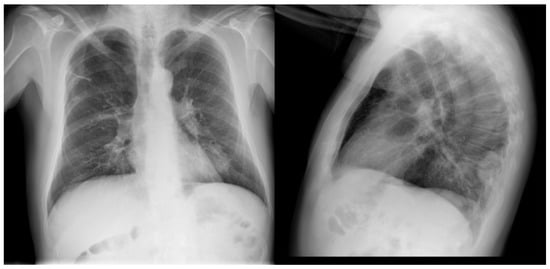

| PET-CT | March 2021 | Initial diagnosis, staging | - Hilar adenopathy compatible with malignancy (SUVmax 20.7). - Hypermetabolic mass (SUVmax 18.3) in the left lower lobe measuring 3.2 × 5.1 cm compatible with malignancy. - Calcified granuloma in right upper lobe. - Abdomen without foci of pathological uptake. |

| PET-CT | October 2021 | Re-evaluation | - Hypermetabolic mass (SUVmax 24.72) in left lower lobe of 4.2 × 3.5 cm. - Complete response of the hilar adenopathies, without pathologic uptake. - Focal increase of FDG in pseudonodular formations in mesenteric fat, up to SUVmax 12.48, in relation to mesenteric panniculitis. |

| PET-CT | October 2022 | Re-evaluation | - Morphometabolic progression of pathologic adenopathies observed on staging PET in March 2021 that had normalized in October 2021, SUVmax 19.5. - Complete morphometabolic response of primary left lower lobe neoplasm, currently 1.8 cm and SUVmax of 2.6. - Signs of mesenteric panniculitis, with practical metabolic normalization of the FDG uptake foci at this level that were visualized in the previous PET scan of Oct/21. |

| PET-CT | April 2023 | Severe abdominal pain that had consulted 4 times in the emergency room | - Hypermetabolic persistence of adenopathies in the right cervical chain, lower paratracheal and right pulmonary hilum with dissociated response, some have progressed and others have improved. - Signs of mesenteric panniculitis, visualizing increased pseudonodular formations, several with FDG uptake up to SUVmax 7.50, not present in the previous study. |